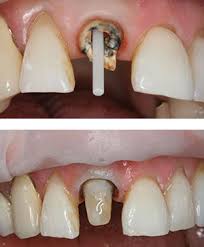

Smile Transformation Journey

Case Highlights. Visible Results